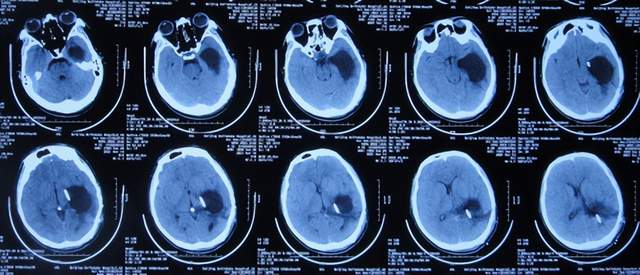

出院后5个月即2021年9月中旬,出现偶尔头痛的症状,因此于出院后7个月后即2021年11月10日,第2次来到李小勇脑脊液科;入院时:时有头痛(图-26),身体其他正常;查头颅CT示左侧颞角扩张(图-27)。

图-26:2021年11月10日入院时

图-27:入院时头颅CT

入院后2天即2021年11月12日,给予了颞角分流管调整术;术后第2天查头颅CT示颞角仍扩张(图-28)。

图-28:2021年11月14日头颅CT

入院治疗14天即2021年11月24日,查头颅CT示颞角缩小(图-29),患者头痛基本消失(图-30)。

图-29:2021年11月24日头颅CT

图-30:2021年11月24日

2022年1月4日(李小勇脑脊液科第2次治疗55天)出院。出院时:头痛已消失1月余(图-31),身体一切正常,查头颅CT示未见异常(图-32)。

图-31:2022年1月4日出院时

图-32:出院时头颅CT

四、第3次在李小勇脑脊液科治疗过程和结果

第2次出院后5个月即2022年6月初,再次出现头痛的症状,因左侧颞角再次增大,于2022年7月18日,第3次来到李小勇脑脊液科治疗。入院时:仅时有头痛。查头颅CT示左侧颞角扩张(图-33)。

图-33:2022年7月18日头颅CT

入院后3天即2022年7月21日,显微镜下颞角脉络丛切除术+分流管调整术,留置引流一根;术后查头颅CT示脑室内有2根管(图-34)。

图-34:2022年7月21日头颅CT

入院后11天即2022年7月29日(脉络丛切除术后8天),查头颅CT示引流术后状态(图-35)。

图-35:2022年7月29日头颅CT

入院治疗12天即2022年7月30日(脉络丛切除术后9天),给予拔除了原脑室腹腔分流管,查头颅CT示脑室内有一根管(图-36)。

图-36:2022年7月30日头颅CT

入院治疗21天即2022年8月8日(脉络丛切除术后18天),查头颅CT未见异常(图-37),患者身体无异常(图-38)。

图-37:2022年8月8日头颅CT

图-38:2022年8月8日

2022年8月22日(脉络丛切除术后32天),查头颅CT示颞角未见扩张(图-39),给予夹闭引流管。

图-39:2022年8月22日头颅CT

夹闭引流管14天后即2022年9月5日(脉络丛切除术后46天),查头颅CT示未见异常(图-40)。

图-40:2022年9月5日头颅CT

夹闭引流管15天后即2022年9月6日(脉络丛切除术后47天),给予拔除了脑室外引流管,当天查头颅CT示脑室基本正常(图-41);患者身体无异常。

图-41:2022年9月6日头颅CT

拔除了脑室外引流管后6天即2022年9月12日, 查头颅CT示未见异常(图-42);身体一切正常,于2022年9月16日出院。

图-42:2022年9月12日头颅CT

五、出院后随访

出院后3个月即2022年11月,在当地医院查头颅CT示无异常(图-43);本人叙述身体一切正常。

图-43:2022年11月头颅CT